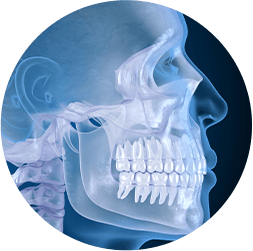

Oral Surgery

bone grafting

If you need to improve the strength of your jawbone, or if you are considering implant-supported dentures, make an appointment with Dr. Michel Raad to learn more about bone grafting. This treatment can restore bone mass to your jaw that has been lost due to one or more missing teeth and even give you a healthier smile.